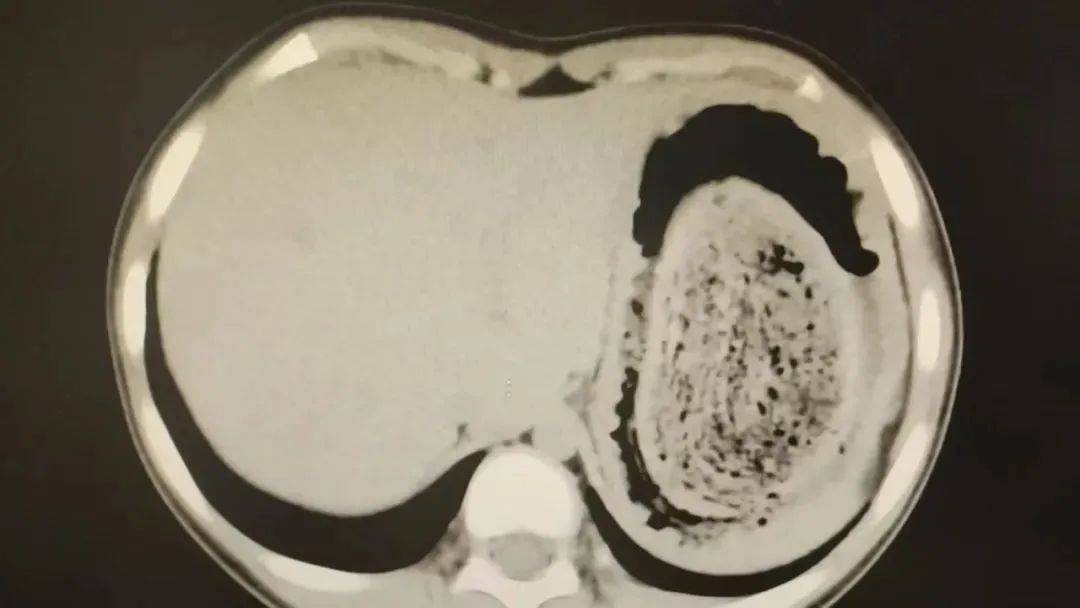

结果出来时,医生都惊呆了:小可的胃里,塞满了成团的头发,几乎占了胃容量的四分之三皇冠信用網在线注册。大量不能消化的物质,在胃酸的作用下发生变性,并与食物及其他物质结合形成团块,慢慢变成坚硬的“胃石”。

2024年10月,11岁女孩欢欢(化名)因腹痛难耐紧急送到医院,而就在两个月前,欢欢的父母发现她在拔自己的头发,偷偷吃掉皇冠信用網在线注册。经检查,医生发现她胃腔和肠管里有大块的毛絮状结石,几乎占据整个胃部。最终,一块长38厘米、宽15厘米、厚10厘米的毛发结石被取出。